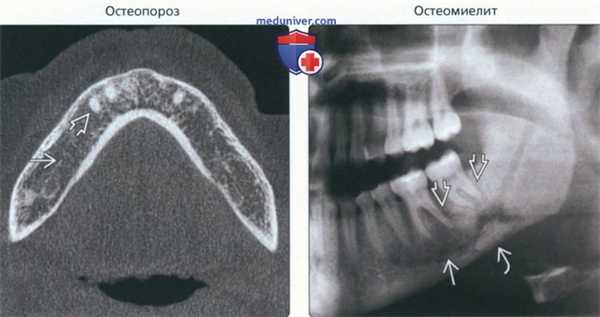

(Слева) На аксиальной КЛКТ у женщины 90 лет с остеопорозом определяются признаки остеопении нижней челюсти: разрежение трабекул, истончение или отсутствие твердой пластинки вокруг оставшихся зубов.

(Справа) На панорамной рентге нограмме определяются смешанные (литические и склеротические) изменения нижней челюсти слева. Обратите внимание на отсутствие твердой пластинки возле пораженных зубов и компактной кости вокруг нижнечелюстного канала. У нижнего края определяется секвестрация.

• Остеопороз:

о Визуализация:

- Генерализованное снижение плотности костей

- Возможно истончение или отсутствие кортикальных/твердых пластинок

• Остеомиелит:

- Плохо отграниченные смешанные литические и склеротические изменения

- Секвестрация и пластинчатая периостальная реакция